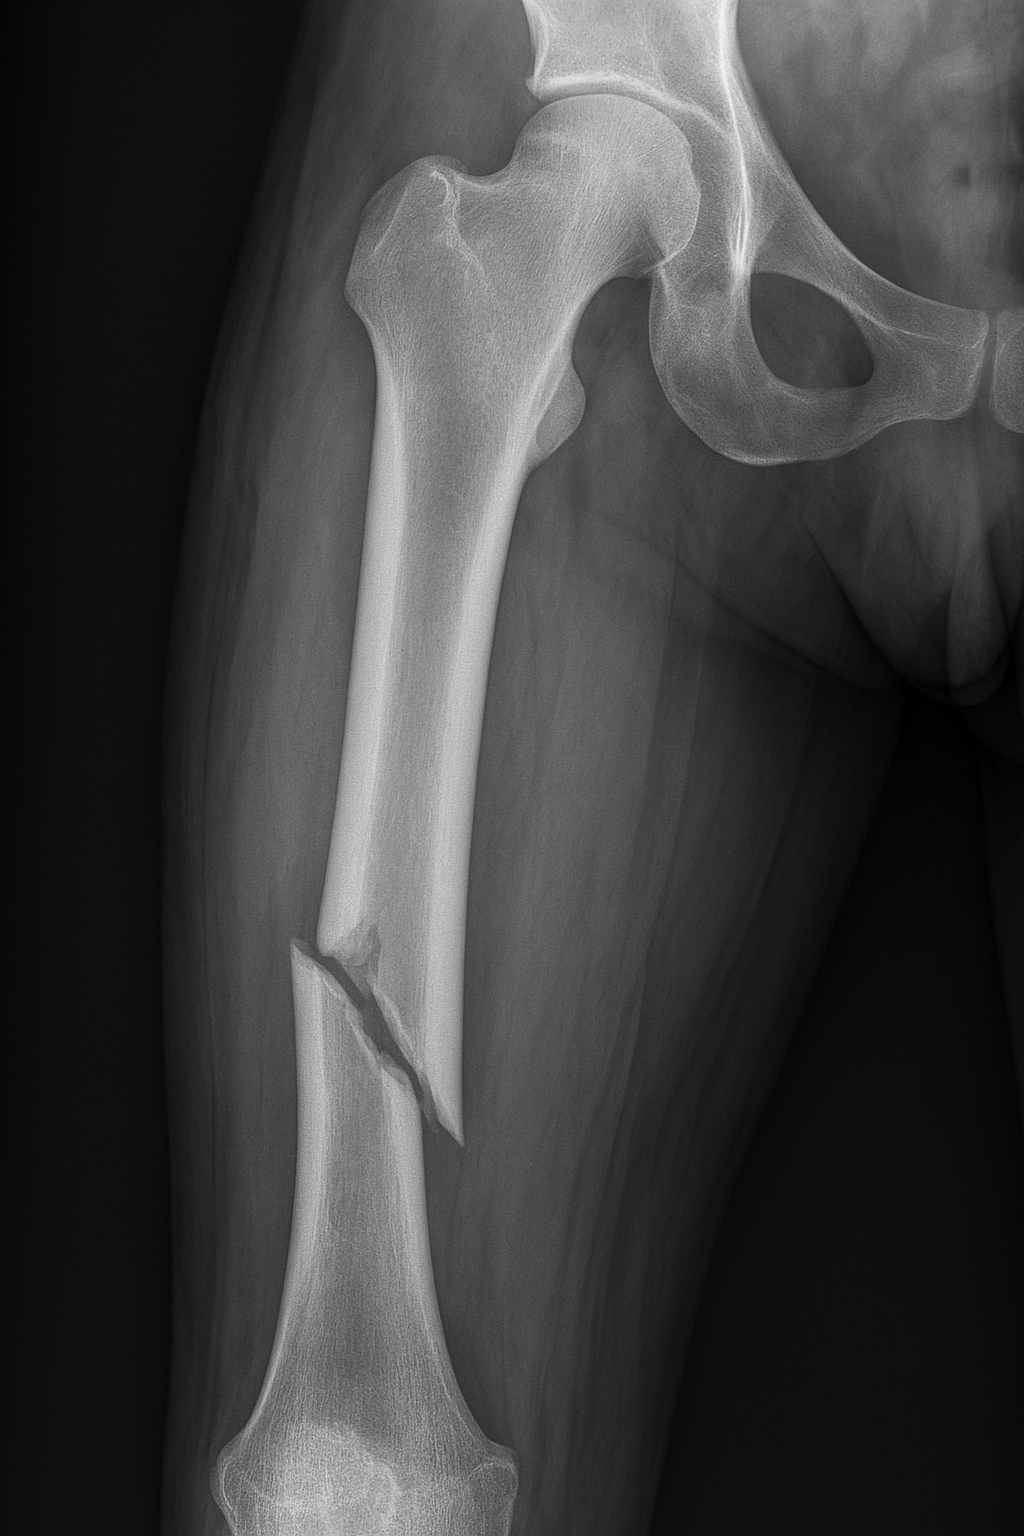

The story is told that one of Margaret Mead’s students asked her what she considered to be the first sign of civilization. The student expected the anthropologist to point to clay pots, tools for hunting or various societal or religious artifacts. Instead, Mead pointed to a healed femur found in an archeological site, dating back 15,000 years. This was the first

evidence of civilization, she claimed.

A femur is the longest bone in the body, linking hip to knee. Take away some of the benefits of modern medicine and it takes about six weeks of rest for a fractured femur to heal. This particular bone had been broken and had healed. Mead explained that in the animal kingdom, if you break your leg, you die. You cannot run from danger, you cannot drink or hunt for food. In fact, if you were wounded in this manner, you became food for other animals. If you were to stand still for your bone to heal, you’d definitely be the main course on some other animal’s dinner menu. Another animal… that’s right. The question being asked was what separates us – humanity – from other animals? Why was this healed bone the key to understanding when we moved from animal to caring people?

A broken femur that has healed, explained Mead, is evidence that another person took time to stay with the injured person, bound the wound, carried the person to safety and tended to them through recovery. A healed femur indicates that someone has helped a fellow human, rather than abandoning them to save their own life.